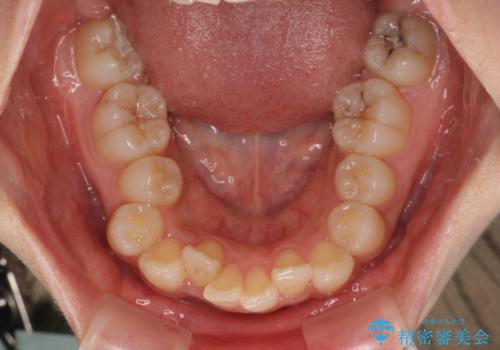

- 上顎前歯の突出感を気にして来院された患者様です。

上下左右第一小臼歯4本を抜歯して、積極的に口元を引っ込めるよう、ワイヤー装置にて矯正治療を行うこととしました。